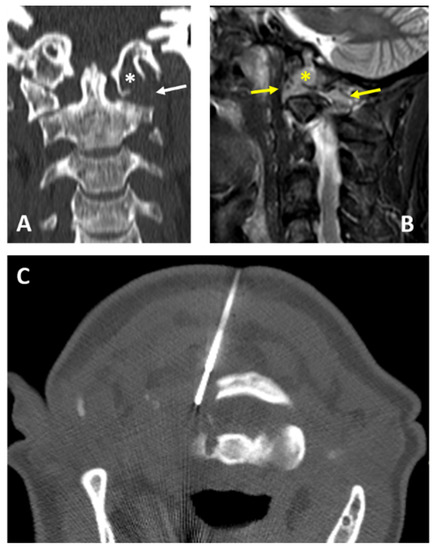

| 1 | 18, M | C2 | Osteolytic | 14 | No | Posterior | Aneurismal bone cyst |

| 2 | 71, M | C2 | Osteolytic | 14 | No | Posterior | Multiple myeloma |

| 3 | 49, M | C1 | Osteolytic | 14 | No | Posterior | Aggressive hemangioma |

| 4 | 64, F | C2 | Osteolytic | 14 | Yes | Lateral | Multiple myeloma |

| 5 | 64, F | C1 | Osteolytic | 14 | No | Posterior | Metastasis (breast cancer) |

| 6 | 40, F | C2 | Osteolytic | 14 | No | Posterior | Metastasis (breast cancer) |

| 7 | 39, M | C1 | Osteolytic | 14 | No | Posterior | Multiple myeloma |

| 8 | 16, M | C2 | Osteolytic | 14 | No | Posterior | Aneurismal bone cyst |

| 9 | 79, M | C2 | Osteolytic | 14 | Yes | Lateral | Non-diagnostic |

| 10 | 23, M | C1 | Osteolytic | 14 | No | Posterior | Blood and fibrin (non-diagnostic) |

| 11 | 73, M | C1 | Mixed | 14 | No | Posterior | Metastasis (prostate cancer) |

| 12 | 52, F | C0 and C1 | Osteolytic | 14 | Yes | Posterior | Multiple myeloma |

| 13 | 28, F | C1 | Osteolytic | 14 | No | Posterior | Aneurismal bone cyst |

| 14 | 72, F | C1 and C2 | Sclerotic | 12 | No | Posterior | Pseudogout |

| 15 | 51, F | C1 and C2 | Osteolytic | 14 | Yes | Posterior | Rare giant cells (non-diagnostic) |

| 16 | 86, F | C0 | Osteolytic | 12 | No | Posterior | Metastasis (breast cancer) |